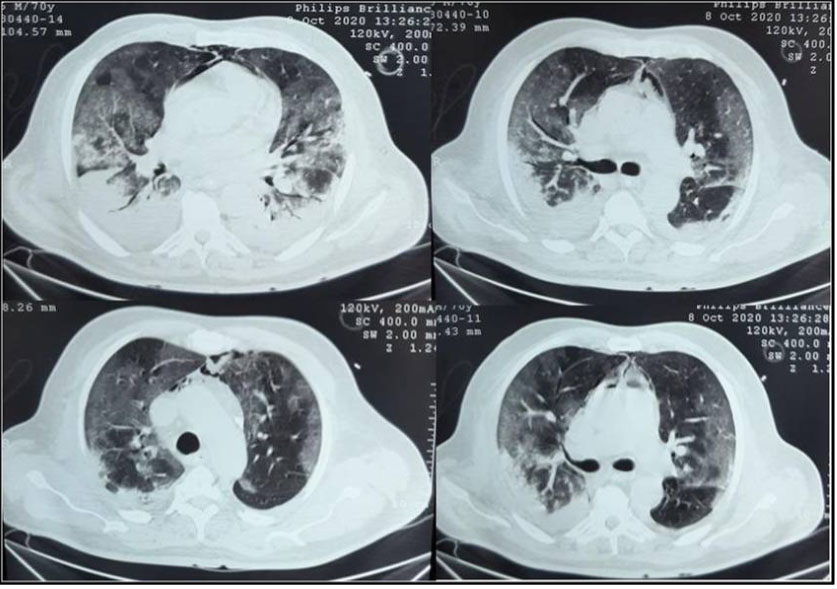

A 70-year-old male patient with past medical history of diabetes type 2 was admitted in our ICU for acute respiratory failure due to COVID-19 pneumonia with diffuse bilateral ground-glass opacities on non-contrast chest CT scan. Upon admission, his respiratory rate was of 26 breaths/min, SpO2 at 88% under 15 L/min of oxygen with non-rebreather mask, he was conscious with stable hemodynamic state. Blood test results showed a CRP of 90 mg/L, leukocytes of 15,000/mm3. His ABG showed pH: 7.38, PaO2: 49 mmHg, PaCO2: 29 mmHg, HCO3−: 17.2 mmol/L and SaO2: 83%. The patient was maintained under 15 L/min of oxygen with SpO2 95% and RR 20–25 breaths/min, put under antibiotics; Dexamethasone 6 mg/12 h, anticoagulation and prone positioning. After 24 hours of ICU stay, the patient was intubated in front of severe acute respiratory failure. The trachea was intubated using direct laryngoscopy with no difficult airway management, no bougie or stylet were used, 7.5 cm tracheal tube was inserted, the patient was ventilated with protective ventilation with VAC mode (Vt: 6 mL/kg of PBW, PEP: 10 mmHg, RR: 26 breaths/min, and FiO2: 100% with PIC at 28, P.Plat 25, and DP at 15); and immediately put under continuous infusion of sedation and muscle blockers. The evolution was marked initially by the deep hypoxemia with PaO2/FiO2 at 100, instable hemodynamic state and elevated PIC at 45 cmH2O. Then in front of the slight improvement of the respiratory and hemodynamic state, a control non-contrast chest CT scan was performed at day 6 after invasive mechanical ventilation showing: mild to moderate PM associated to mild bilateral pleural effusion with stable aspect of the ground-glass opacities associated to inferior alveolar consolidation (Figure 6). In front of the maintained stable hemodynamic state, we decided the conservative therapy with reducing airway pressure (PEEP at 5 cmH2O) and close monitoring. The patient was maintained under protective ventilation, sessions of prone position with difficult weaning. The evolution was marked by a septic shock, and he passed away at 18 of ICU stay.

Figure 6: Control non-contrast chest CT scan showing: mild to moderate pneumomediastinum associated to mild bilateral pleural effusion with stable aspect of the ground-glass opacities associated to inferior alveolar consolidation.